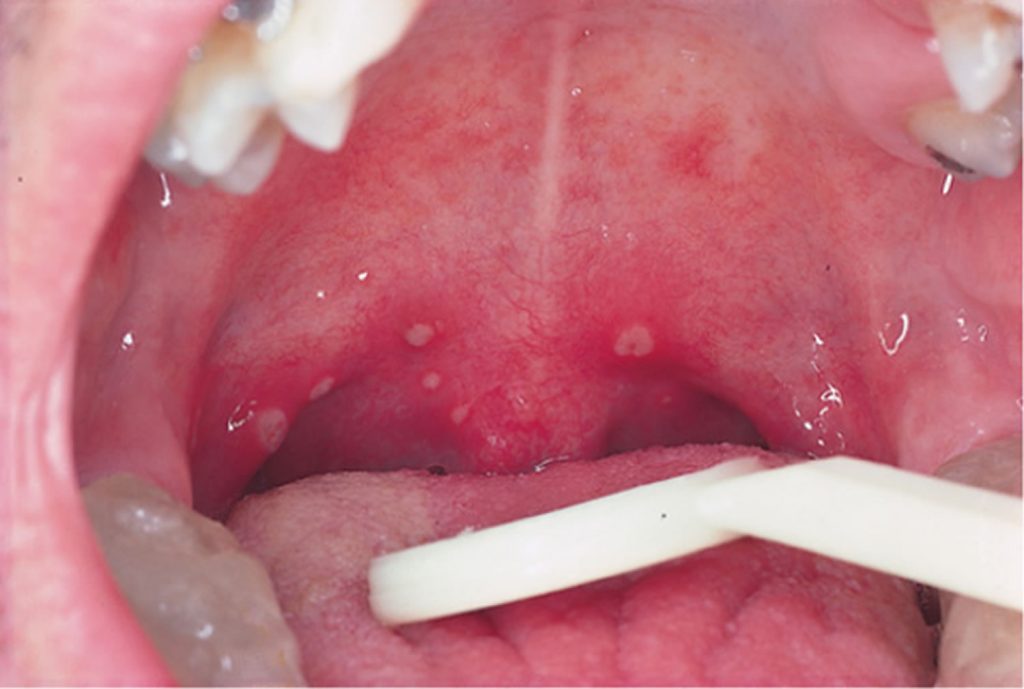

HERPANGINA – COXSACKIE A16

- Herpangina